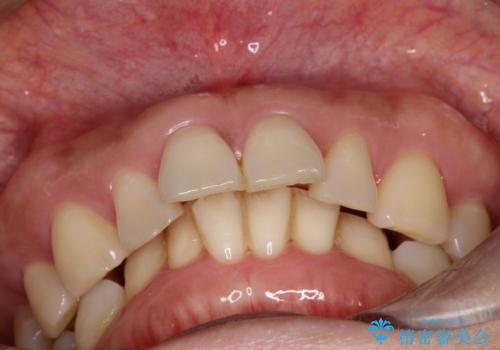

【インビザライン】出っ歯を治したい

- 前歯が出ていることを主訴に来院されました。

インビザラインにて臼歯部の遠心移動及びIPRを行なっています。

叢生量が多いケースでしたが、綺麗な歯並びとなり患者様にも満足していただきました。